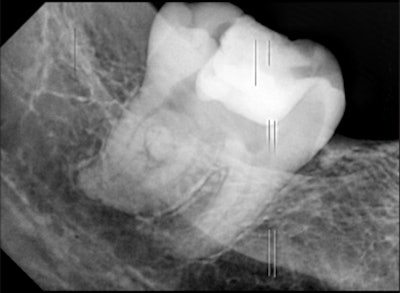

He underwent an intraoral x-ray that showed fused molars with an irregular morphology and a wide mesiodistal width. The 2D view offered by the x-ray made it difficult to identify the demarcation between the pulp chamber of the third molar and the supernumerary tooth. Also, clinicians could not ascertain the root canal configuration of the tooth, according to the report.